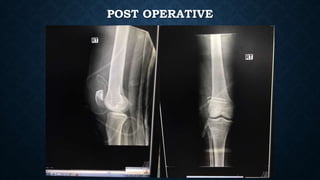

POST OPERATIVE